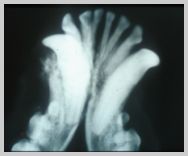

DV view of cat with fractures to

right mandible